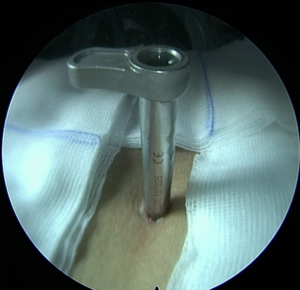

Πλάγια προσπέλαση

Πρόκειται για μια ακόμα πιο ειδική μέθοδο, κατά την οποία εισερχόμαστε μέσω του μεσοσπονδύλιου τρήματος και αποκτούμε πρόσβαση κατευθείαν στην δισκοκήλη χωρίς να χρειάζεται αφαίρεση οστικού τμήματος. Αποτελεί την λιγότερο επεμβατική μέθοδο όλων στην σπονδυλική στήλη, αφού χρησιμοποιεί φυσικά τρήματα για την είσοδο στον σπονδ. σωλήνα.